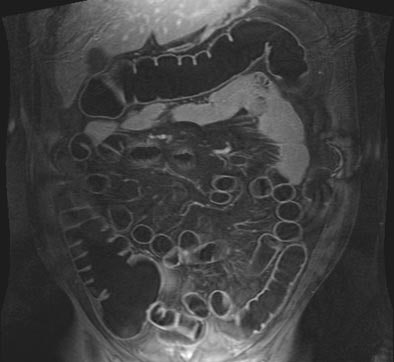

| T1-weighted GRE MR colonography images of the same patient. Top: water-filled colon following rectal enema. Bottom: study obtained on another day, following rectal insufflation with room air. Images courtesy of Dr. Thomas Lauenstein. |

Another new study by the Essen radiologists sought to determine if either air or water as a colon insufflation agent performed better in dark-lumen MRC (Journal of Magnetic Resonance Imaging, February 2004, Vol. 19:2, pp. 216-221).

The group performed dark-lumen MRC followed by conventional colonoscopy on 50 patients suspected of having colorectal pathologies, who were randomized into two groups of 25 patients undergoing either tap water or room-air insufflation prior to imaging. In addition, five healthy volunteers agreed to undergo MRC twice, once with water and once with room air, prior to the conventional exam.

MR data were acquired using a combination of two surface coils on a 1.5-tesla Magnetom Sonata scanner (Siemens Medical Solutions, Erlangen, Germany). T1-weighted 3-D gradient-echo images (96 slices, effective slice thickness 1.54 mm) were acquired in the coronal plane, and sequence parameters included TR/TE 3.1/1.1 msec, flip angle 12º, FOV 450 x 450. Then a paramagnetic contrast agent, Gd-BOPTA, was administered intravenously (0.2 mmol/kg) and the same imaging sequence was repeated after a 75-second delay.

The image-quality rating trended better with air distension (1.2 for air versus 1.3 in water among the volunteers), but the difference wasn't statistically significant. However, the use of air produced significantly better colonic distension than water (p<0.05), with a mean rating of 1.07 for air compared to 1.31 for water among the patients.

In patients or volunteers, artifacts were not a problem with either air or water distension, although there were a few artifacts related to motion or wrapping. However, there were statistically significant differences in the contrast-to-noise ratio, with a mean of 43.5 for air distension and a mean of 36.3 (p< 0.05) for water overall. Preferences among the five volunteers were inconclusive: two preferred each method, and one preferred neither.

Moreover, eight of nine lesions were detected on water-filled MRC, and no lesions were missed when air distension was used. And, they said, the use of ultrashort (0.6-second) echo times virtually eliminated the presence of susceptibility artifacts in the presence of air distension because "there is simply not time for disphasing to occur. Thus it was not surprising that image quality of air- and water-distended datasets did not reveal a statistically significant difference."

"We conclude that MRC...can be performed using either air or water as a distending agent," they wrote. Still, "slightly better CNR and improved distension of the rectum and sigmoid colon seem to favor air distension."